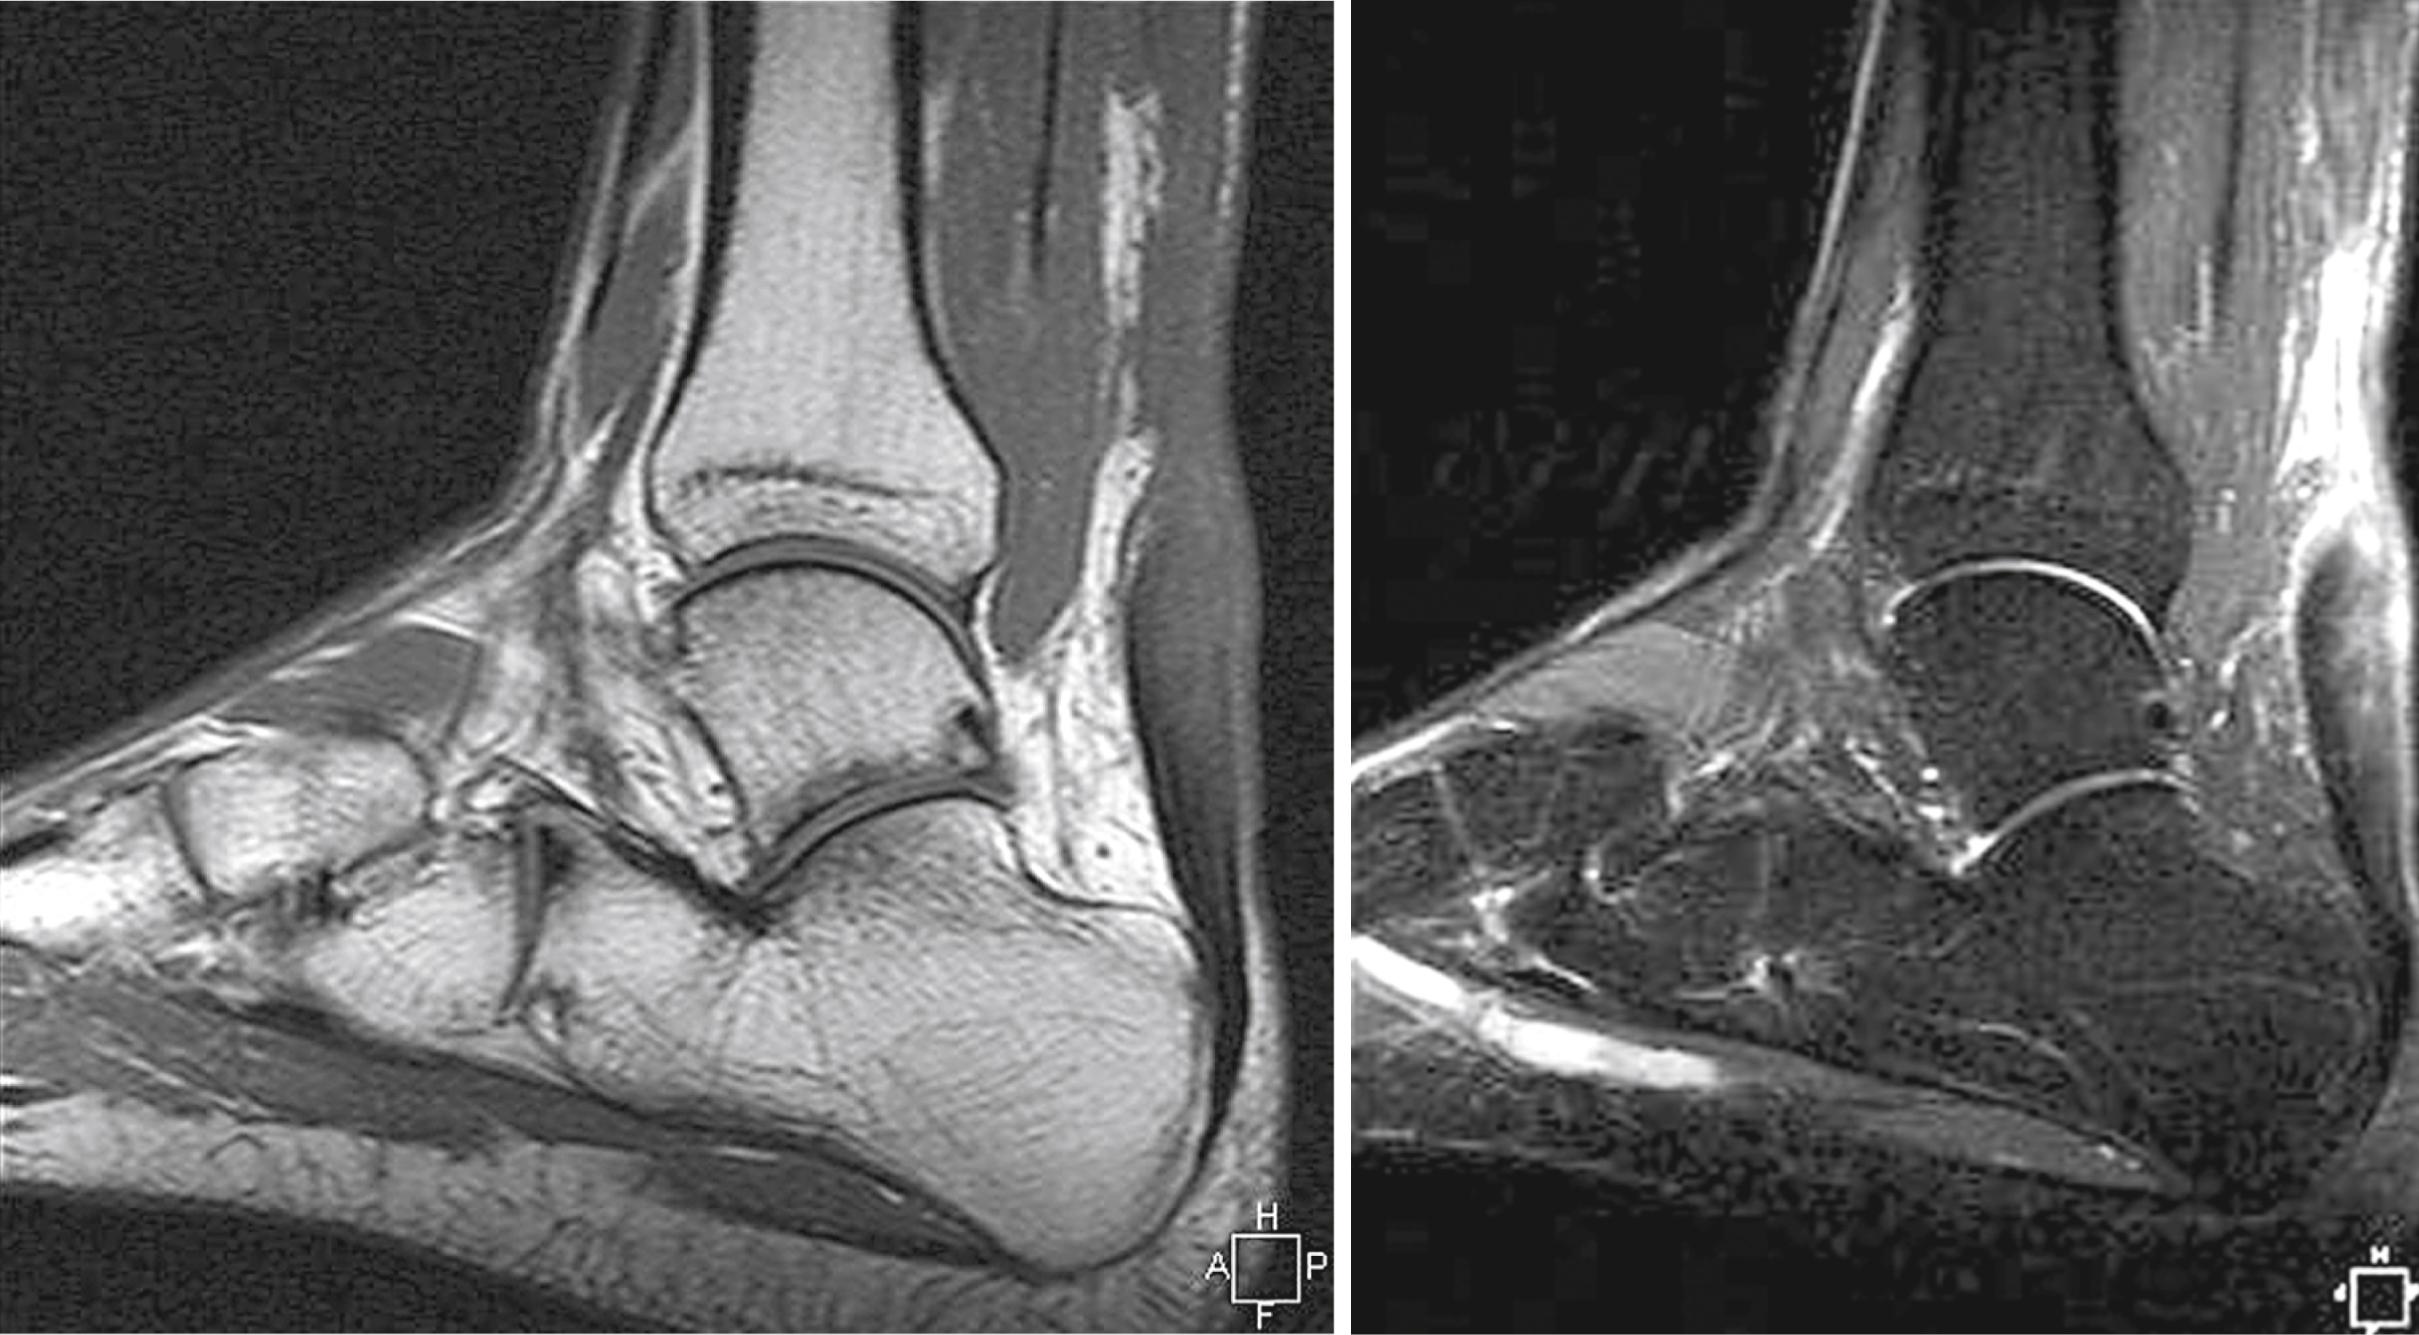

The definition of a “chronic” rupture has ranged from those diagnosed and treated more than 48 hours after injury to those diagnosed and treated up to 2 months after injury. There appears to be some consensus that a rupture diagnosed 4 to 6 weeks after injury should be considered a chronic rupture and that these are more difficult to treat than acute injuries. At about 1 week after rupture of the Achilles tendon, any space between the tendon ends fills with scar tissue. If left untreated, the tendon heals elongated, leaving the patient unable to push off on the affected side. Running, jumping, and activities such as ascending or descending stairs are severely compromised. Calf atrophy usually is present, the Achilles tendon often loses its normal contour, and a visible tendon defect may be present. MRI can be helpful to estimate the gap between the ruptured ends of the tendon ( Fig. 48.23 ). Chronic ruptures appear as an area of low-intensity signal on T1-weighted images and alteration in T2-weighted signal.

FIGURE 48.23, MRI appearance of chronic Achilles tendon rupture.

If posterior heel pain, swelling, or functional impairment is disabling, delayed repair or reconstruction is indicated. In most active adults, repair is preferable but often is not possible. For ruptures more than 3 months old, treatment depends on the patient’s physiologic age, activity level, and amount of functional impairment. A number of techniques have been described for reconstruction of a neglected Achilles tendon rupture ( Box 48.4 ). If the tendon defect is less than 3 cm after debridement and the injury is less than 3 months old, direct repair often is possible. If, however, the tendon gap is more than 3 cm (more common), additional techniques must be used, such as local tissue transfer, tissue augmentation, synthetics, and allografts.